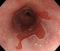

内視鏡所見と病理組織像の1対1対応が可能な症例を公募いたします。主にLSBEに発生した早期癌(HGDを含む)を対象としますが、興味深い症例であればSSBE癌でも結構です。採否は世話人へご一任ください。

症例呈示希望者は応募用紙に記入の上、代表的な内視鏡(2枚)、切除標本(新鮮、固定)、切り出し図、マッピング、代表的組織像とともに、Barrett 食道研究会事務局 barrett.shinshu@gmail.comへお申し込み下さい(10MB以下でお願い致します)。

2026年1月24日開催の第19回研究会でご提示した検討症例です。 (画像をクリックすると拡大します)